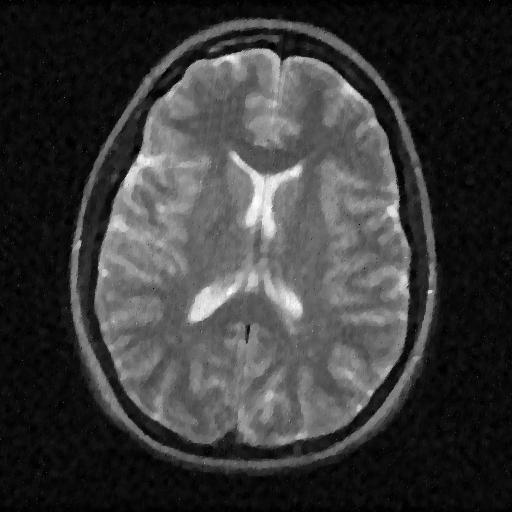

Although we have not explicitly written the theory here, the recovered images in Fig. 11 show the results when using a TV minimization instead of the analysis.

The results were obtained from a spherical beam illuminating the input image. The measurements are obtained by sampling ( samples) of the Fourier coefficients at random iid from a Gaussian distribution. Again, some Gaussian noise with variance is added to every measurements.

| analysis | Sum of Square fusion | Fused analysis | Fused total variation | |

|---|---|---|---|---|

| SSIM | ||||

| PSNR | ||||

| error |

As presented in these examples, our method is capable of handling highly complex signals in potentially many dimensions yet keeping a very low number of samples taken. We can also empirically verify that the presented approach enjoys more robustness to noise and variations in scene illuminations than other known methods.